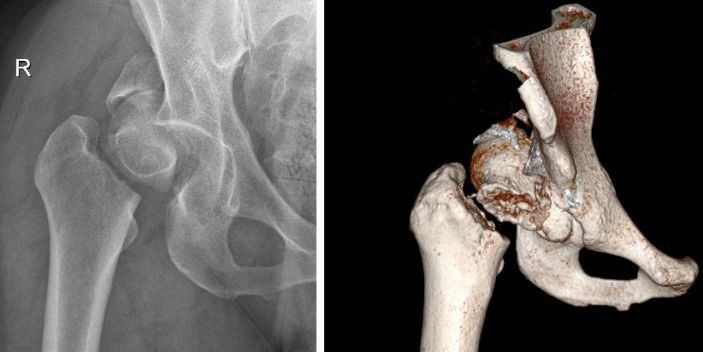

△術前

患者張某,男,37歲,燎原鎮人,體重180斤,4月19日騎自行車時不慎摔倒,右臀部着地,立即感到右臀部疼痛,右下肢活動障礙。在當地診所拍片顯示右股骨頸骨折,随來我院住院治療。經我院CT檢查,診斷爲右髋臼、右股骨頭、右股骨頸三處部位粉碎性骨折。

患者右髋關節損傷嚴重,任一處骨折的手術複位都具有很大挑戰性,而三個部位同時粉碎性骨折的治療難度可想而知。術中骨折達到解剖複位的難度大,術後出現股骨頭壞死、創傷性關節炎的風險極大,緻殘率極高。此類型的骨折對任何一個專業骨科醫生都是很大的挑戰,甚至就直接選擇進行全髋關節置換(非保髋的手術方案),但患者年紀較輕,以後就要面對多次翻修手術(人工關節的壽命大概20年)。